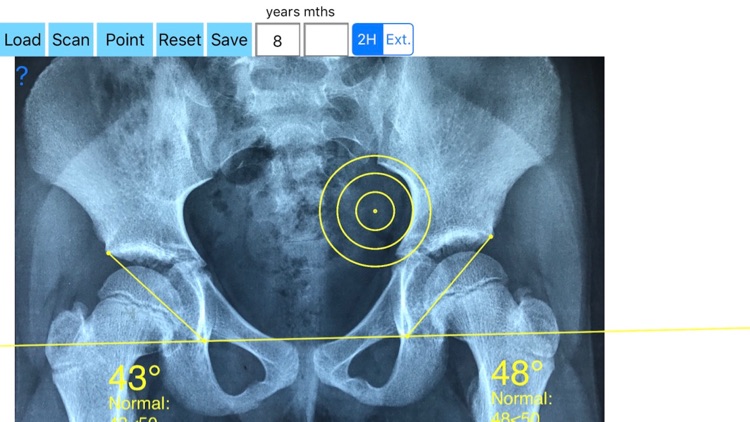

What is it about?

The diagnosis of hip dysplasia, the prognosis, the evaluation of different methods of treatment is based mainly on X-rays of the hip joint. For the objective evaluation of hip dysplasia in everyday orthopaedic care the acetabular index (AI) or the Centre-edge angle (CE) are frequent measured. But the measurement of AI is not valid index for acetabular Dysplasia in children over 8 years of age and in cases with subluxation of the femoral head where the centre-edge angle (CE) is not accurately calculated. The acetabular angle of Sharp (AA) is especially designed for theses cases. The acetabular angle of Sharp (AA) is formed by a horizontal line connecting the tips of the both pelvic teardrops and by a line connecting the inferior tip of the pelvic teardrop with the most lateral point of the acetabular roof.

Measuring angles in X-rays in clinical settings it is time consuming. Accessory instruments like protractors, goniometers, well sharped pencils, rulers or even transparent papers must be available in a busy everyday practice. Usually you miss or you never had one or another. Also after measurement you have to compare the data that you measure with the normal reference values according to patient age, and decide what could be considered normal in an X-ray of the hip and what is considered pathologic. This way is cumbersome and old fashioned.

-Offers a very convenient way to determine the most accurate possibly lines in order to measure the angles. By the aid of a circular transparent template, the points of interest are marked accurately. The automatically formed lines, drawn between points, measure automatically the angles of interest. The results are printed in degrees. By inputing the age, of the patient in the App, the measured angle is compared with values from normal reference database according to patient age. In case the measured angle is beyond the normal range for that age, the hips are categorised as borderline dysplastic or dysplastic.

The app is a handy tool for an orthopaedic surgeon, radiologist, medical student or resident who wants objectively monitor and determine the severity of dysplasia of the hip. The build-in comparison feature with the normal reference values according to patient age may help decide what could be considered normal or borderline dysplastic or dysplastic. The app is not a simple goniometer, is an enhanced product which offers the ability to compare all the input data with medical reference database. The results are printed on the screen and the hips are categorised as normal or dysplastic according to the AA angle measures respectively. This feature it is particular useful especially in clinical settings where you need a quick results without losing time in looking for reference data according to age variations in huge textbooks.